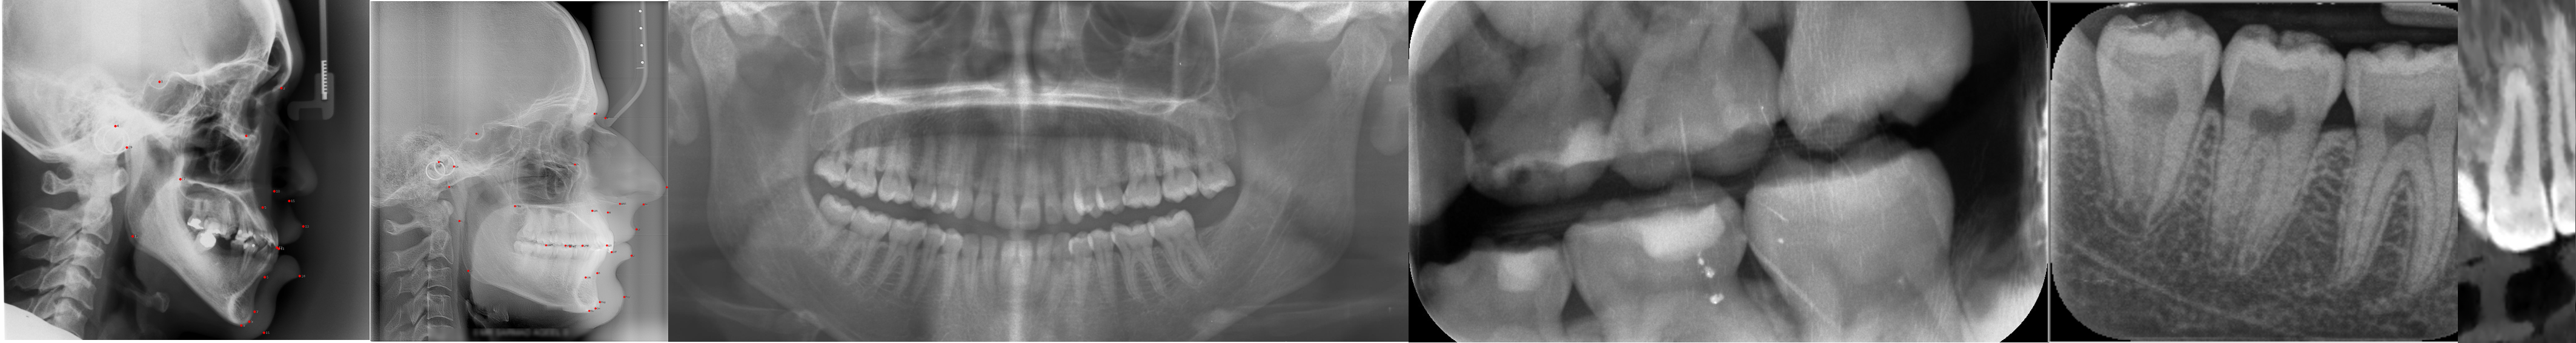

Before joining KCL, I was a Research Assistant at the Institute for AI Industry Research (AIR), Tsinghua University, where I worked with Prof. Zaiqing Nie and Dr. Haibao Yu on autonomous driving perception, planning, and simulation. I obtained my Master’s degree from the Department of Automation, Tsinghua University under the supervision of Prof. Biqing Huang, focusing on computer vision for industrial defect inspection. I received my Bachelor’s degree (with Honours) from Shenyuan Honors College, Beihang University. These experiences built a strong foundation in multimodal perception and machine learning systems, which now support my current research on medical AI for dental diagnosis.

Current Research Focus: multimodal learning, computer vision, and medical AI, with a focus on dental and healthcare applications.

- Dec 2025, Tooth Bone Loss Estimation Based on 3D CBCT Data, Bellairs Workshop on Machine Learning and Statistical Signal Processing for Data on Graphs, Saint James Parish, Barbados.